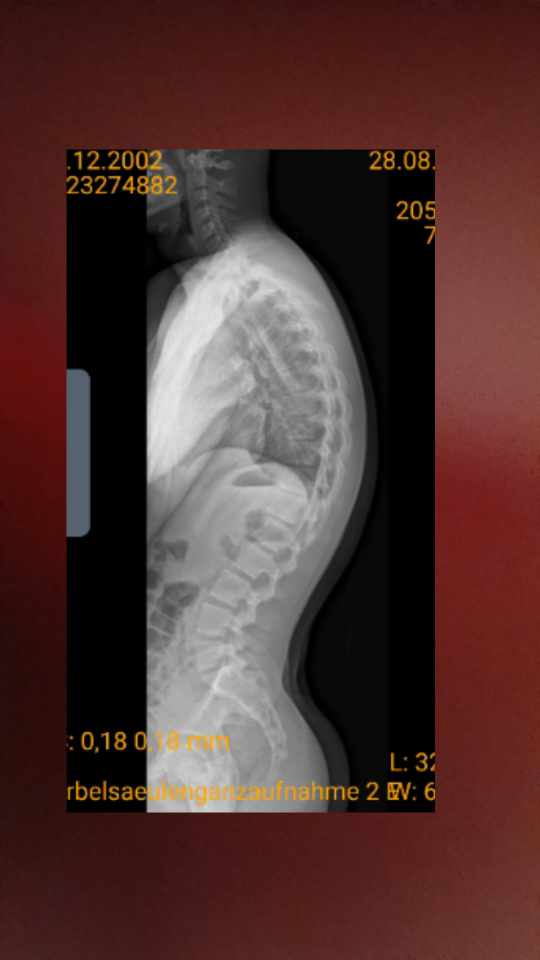

Um mich etwas hier mit zu beteiligen und das zu klären, ob ich auch eine tiefsitzende Hyperkyphose habe, versuche ich jetzt mal die Bilder wo man es erkennen sollte mit 680 Pixel hochzuladen.

Würde mich mal interessieren, was die Experten sagen in welchen Wirbel/Wirbeln die Krümmung wäre, stehend erkennt man es leicht relativ mittig bei mir. Bin der Meinung das es knapp über der LWS ist und daher tiefsitzend. Die Frage beschäftigt mich auch seit längeren und hat auch Einfluss darauf, was ich eventuell noch machen kann neben Schroth zur Verbesserung.

MRT wurde in Februar gemacht und war unauffällig.

- Röntgen 680 Pixel.jpg (71.98 KiB) 31860 mal betrachtet

- Ganzkörper Röntgen 680 Pixel.jpg (40.22 KiB) 31860 mal betrachtet

Bei der Bildqualität der Röntgenganzaufnahme, die man dazu braucht, ist das schwer zu sagen. Man muss die Wirbel durchzählen können, also z. Bsp. von unten die 5 Lendenwirbel 5 bis 1 und dann weiter die Brustwirbel 12 bis 6. Dort befindet sich der normale Scheitelpunkt einer BWS Kyphose, also wo die Krümmung in die andere Richtung geht.

Auf jeden Fall sitzt der Scheitelpunkt nicht "knapp über der LWS". Das wäre ja meine Sitiuation, die ganz anders aussieht. Es scheint eher so, als ob er "relativ mittig", also bei Brustwirbel 6 liegt. Gab es dazu während der REHA keine Anmerkungen?